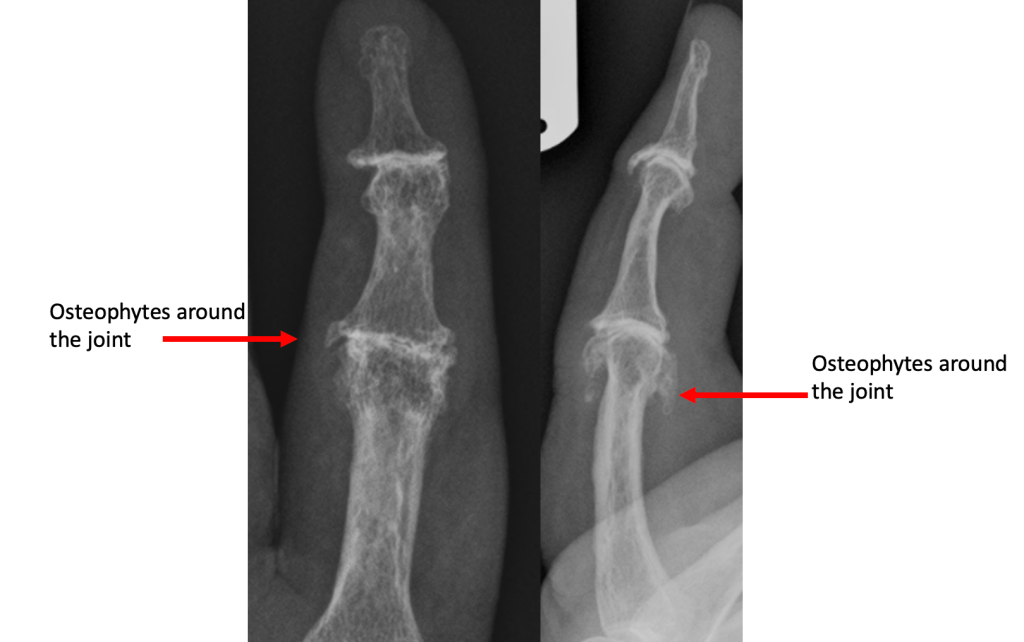

Osteophyte Formation

The stability of a joint depends on the shape and fit of the bone on either side of the joint, and the soft tissues around the joint. In particular, the small joints of the hands have collateral ligaments on either side of the joint, and a tough sheet of fibrous cartilage (volar plate) on the palm side of the joint. These soft tissue structures prevent abnormal movement in the joint.

Where the joint surfaces have worn away, the ligaments and volar plate become slightly too long for the remaining gap, allowing movement of the joint in an abnormal way. The body responds by laying extra bone around the joint in order to make it stable. The extra bone is called osteophyte, and this usually makes the joint stiffen up considerably.